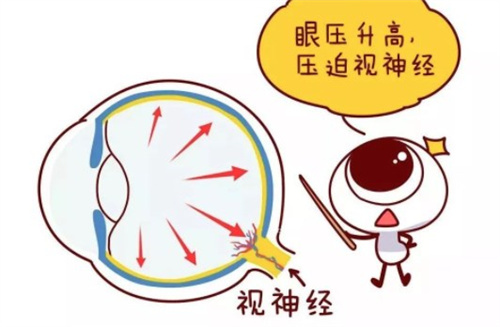

青光眼专科:疑难病例的"克星"

钟晓东医师在青光眼的诊断及手术治疗方面颇有特色,特别擅长复杂性青光眼的个性化治疗,手术成功概率高,患者术后眼压控制稳定。洪斌副高医师则专注于难治性青光眼的综合治疗,尤其擅长青光眼引流阀植入术及联合手术,为晚期青光眼患者保留有用视力。

技术亮点:科室开展的Express微型引流器植入术,较传统手术眼压控制达标率提升30%;选择性激光小梁成形术(SLT)可减少患者长期用药依赖。